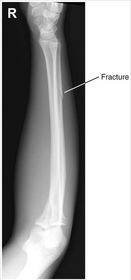

| AP Forearm | not AP - wrist is internally rotated, proximal radius and ulna are superimposed |

| AP Forearm | ANATOMY: entire forearm: wrist joint -> elbow joint CRITERIA: slight superimposition of proximal radius/ulna POSITIONING: CR perpendicular @ midforearm |